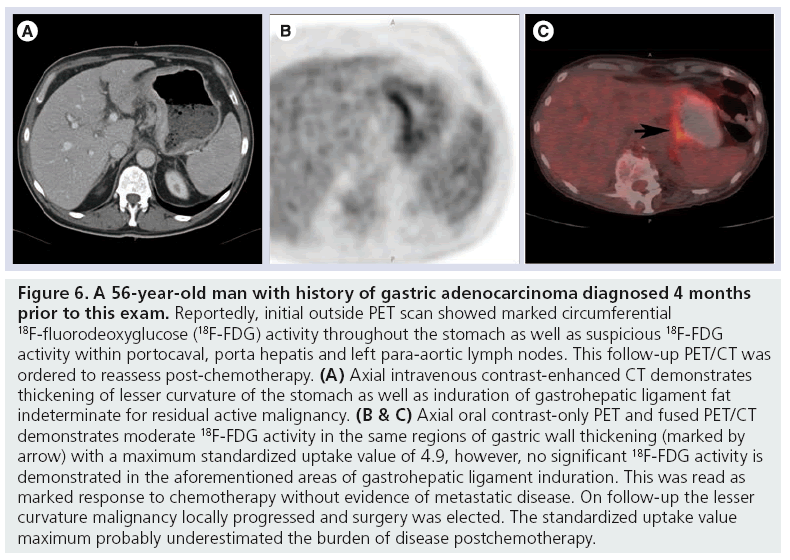

A healthier weight from surgery can help improve or resolve many obesity related conditions such as type 2 diabetes high blood pressure joint pain heart disease and more. Medically treated small gastric ulcer. Left and right gastric veins drain to portal vein. Ugis has a 70 90 detection rate.